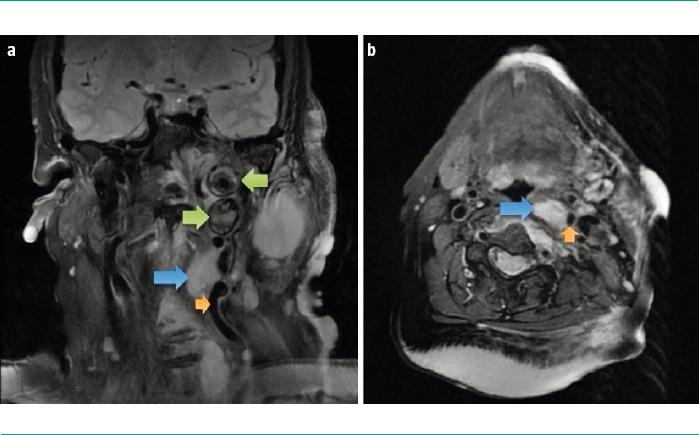

A 67-year-old woman with a genetic diagnosis of NF1 and a history of multiple exeresis of neurofibromas in the left cervical region. The patient presented with a painful flare-up and swelling in the region. A cervical magnetic resonance imaging was performed, which showed signs of plexiform neurinoma growth and a lesion suggestive of aneurysm in the left cervical internal carotid artery. A subsequent computed tomographic angiography confirmed the presence of a thrombosed aneurysm with associated critical stenosis, and identified three additional aneurysms in the proximal left vertebral artery. Given the asymptomatic presentation and adequate haemodynamic compensation, the patient was prescribed a conservative treatment and clinicoradiological follow-up.

一名67岁女性,基因诊断为NF1,有左侧颈部多个神经纤维瘤切除术史。患者该区域出现疼痛发作和肿胀。进行了颈部磁共振成像检查,显示有丛状神经鞘瘤生长迹象以及左侧颈内动脉有一个提示动脉瘤的病变。随后的计算机断层血管造影证实存在一个血栓形成的动脉瘤并伴有严重狭窄,且在左侧椎动脉近端发现另外3个动脉瘤。鉴于患者无症状表现且血流动力学代偿良好,对其进行了保守治疗及临床影像学随访。